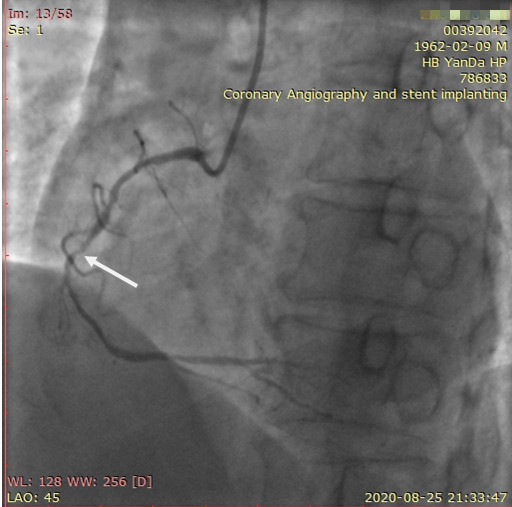

李先生蜘蛛位術前影像

李先生蜘蛛位術后影像

術前,翟光耀主任還親自為李先生復查冠狀動脈造影,造影結果顯示:患者的前降支、回旋支、右冠等冠脈三支嚴重病變、嚴重鈣化,且均為彌漫性長病變,最重處99%以上管腔極嚴重狹窄。翟主任仔細閱讀造影結果后指出:結合李先生的實際情況,雖然微創介入手術難度比較大,但仍可行;李先生心臟三支主干動脈均存在極其嚴重的狹窄,每一支動脈均至少植入2-3枚支架,根據患者的耐受情況,李先生可能需要分3次分別對三支動脈進行介入手術;考慮到李先生路途遙遠,病情嚴重,不宜反復奔波,并且患者迫切要求能夠徹 底解決病痛,在病情允許的情況下,如果手術順利,爭取為患者進行“一站式”手術,一 次 性解決全部三支動脈病變!

手術方案確定之后,在心血管內三科趙景新主任、介入醫學科富孝晨主任的配合下,翟光耀主任親自擔任主刀,分別依次對李先生的三支動脈進行了完全血運重建。由于手術進展順利,李先生術中沒有任何癥狀,耐受良好,于是成功的將三支動脈“一站式”治療!術中,由于李先生左主干遠端分叉處存在嚴重病變,翟光耀主任選擇國際指南推薦的DK-mini-Crush技術,確保了分叉處兩支主干開口均萬無一失。據悉,DK-mini-Crush技術是目前冠脈分叉病變領域最為復雜及難以掌握的介入技術之一,對手術醫生經驗、體力均提出了極大的挑戰。極為擅長復雜介入技術的翟光耀主任卻用嫻熟的技術確保了李先生手術的成功。

冠狀動脈嚴重鈣化合并狹窄病變是冠脈介入的一大難題,血運重建難度大,成功率低,并發癥發生率高,該例患者的成功救治標志著我院冠脈介入水平又躍上了一個新的臺階。